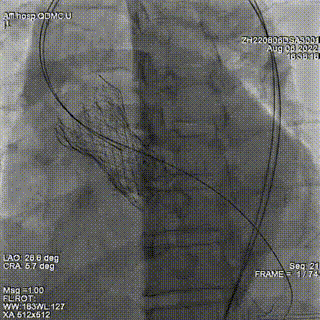

释放第三枚封堵器,选用6mmADOII,释放后造影显示无明显瓣周反流。

术后超声提示微量瓣周反流。